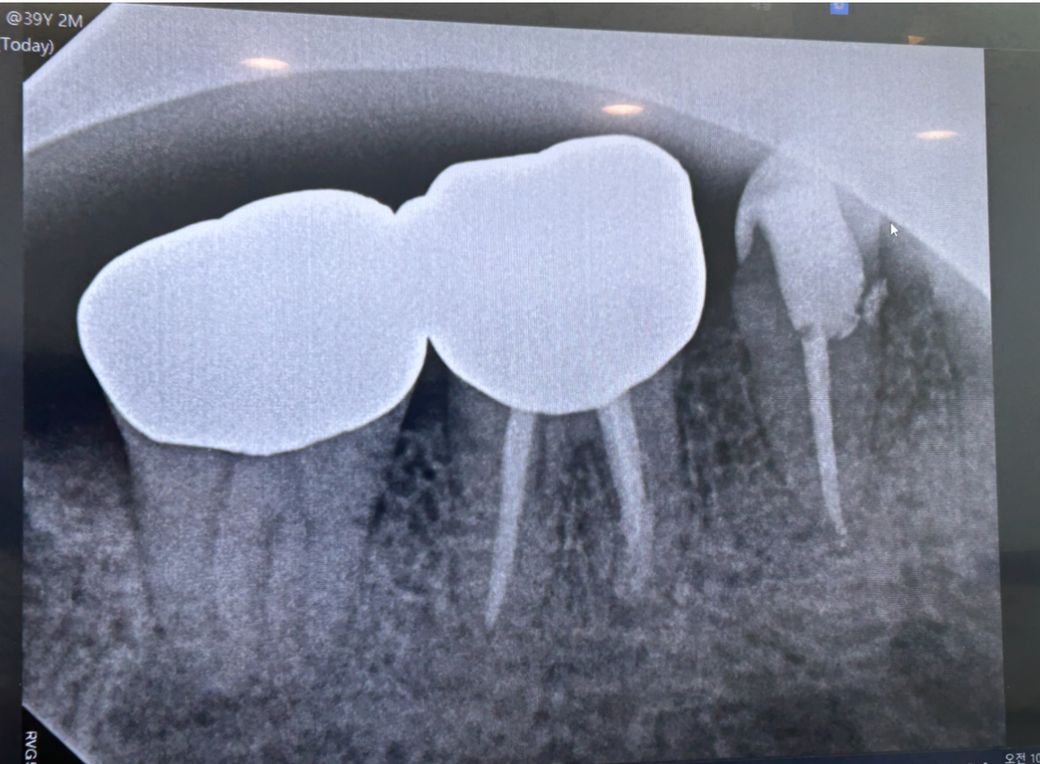

이건 5월 신경치료 하는 중의 엑스레이 입니다

이건 (밑으로)3일전 엑스레이